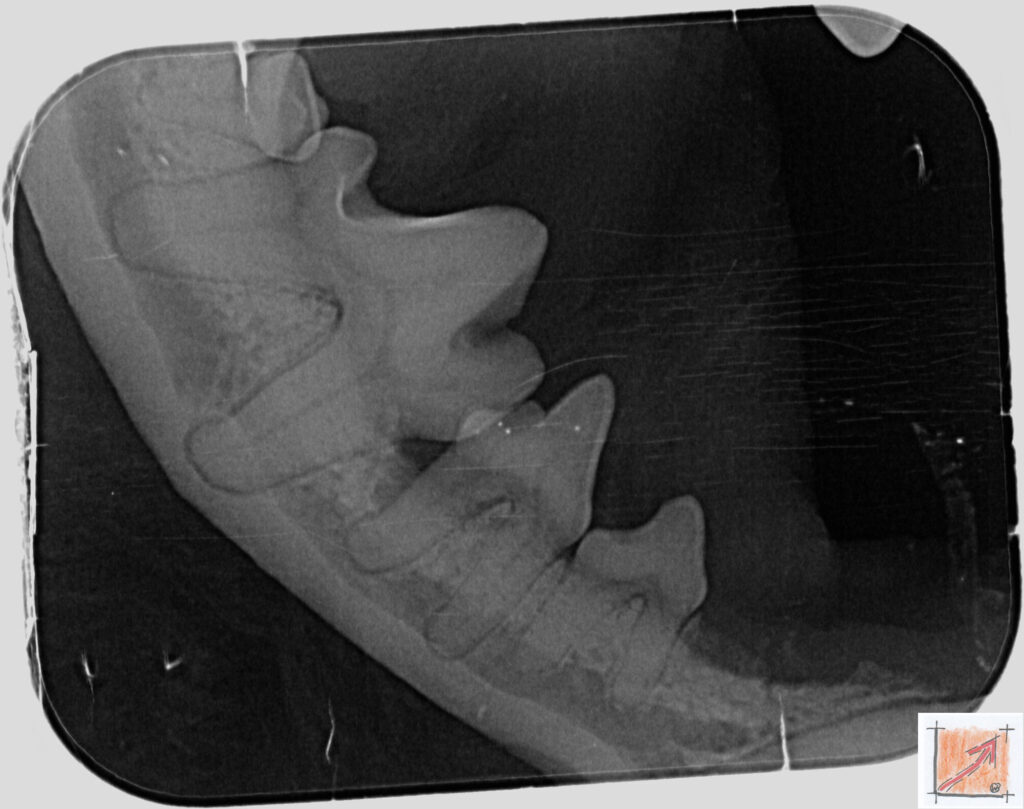

Röntgenbilder vom Thierrischen Orakel bei der Zahn-OP:

Warum Dentalröntgen beim Chihuahua lebenswichtig ist:

Ein Blick hinter die Kulissen von Chihuahua-Zähnen:

In dieser Galerie zeigen wir exklusive intraorale Röntgenaufnahmen einer Zahn-Operation beim Thierrischen Orakel als Chihuahua vom BauFachForum. Während oberflächlicher Zahnstein oft sichtbar ist, verbirgt sich die wahre Gefahr für das Herz meist unter dem Zahnfleischsaum.

Das digitale Dentalröntgen ist der Goldstandard in der modernen Tiermedizin, um parodontale Entzündungsherde und Wurzelabszesse sicher zu diagnostizieren. Für Chihuahuas wie dem Thierrischen Orakel, mit Mitralklappeninsuffizienz ist dieser diagnostische Schritt essenziell. Nur wenn versteckte Bakterienherde an der Zahnwurzel oder mit dem Fachbegriff Apikalabszesse erkannt und saniert werden, kann das Risiko einer bakteriellen Endokarditis oder einfach ausgedrückt einer Herzinnenhautentzündung minimiert werden.

Unsere Aufnahmen von Patienten dem Thierrischen Orakel verdeutlichen den Unterschied zwischen einer rein optischen Zahnreinigung und einer medizinisch fundierten Sanierung unter Röntgenkontrolle.

Chihuahua Mitralklappeninsuffizienz Trachealkollaps:

Wichtig ist im Vorfeld die Zahnhygiene des Chihuahuas. Die Bilder zeigen Dentale Röntgenbilder vom Thierrischen Orakel als Chihuahua-Hund während seiner Zahn-OP. Darstellung von Kieferknochen und Zahnwurzeln zur Diagnose von Parodontitis.

Zahnröntgenaufnahme bei Chihuahua Thierry:

Untersuchung der Zahnwurzeln auf Entzündungsherde als Prophylaxe gegen bakterielle Endokarditis.

Intraorales Dentalröntgen eines Chihuahuas:

Die Bilder zeigen Zähne und Wurzelstrukturen im Unterkiefer zur Planung einer Extraktion bei hochgradigem Zahnstein.